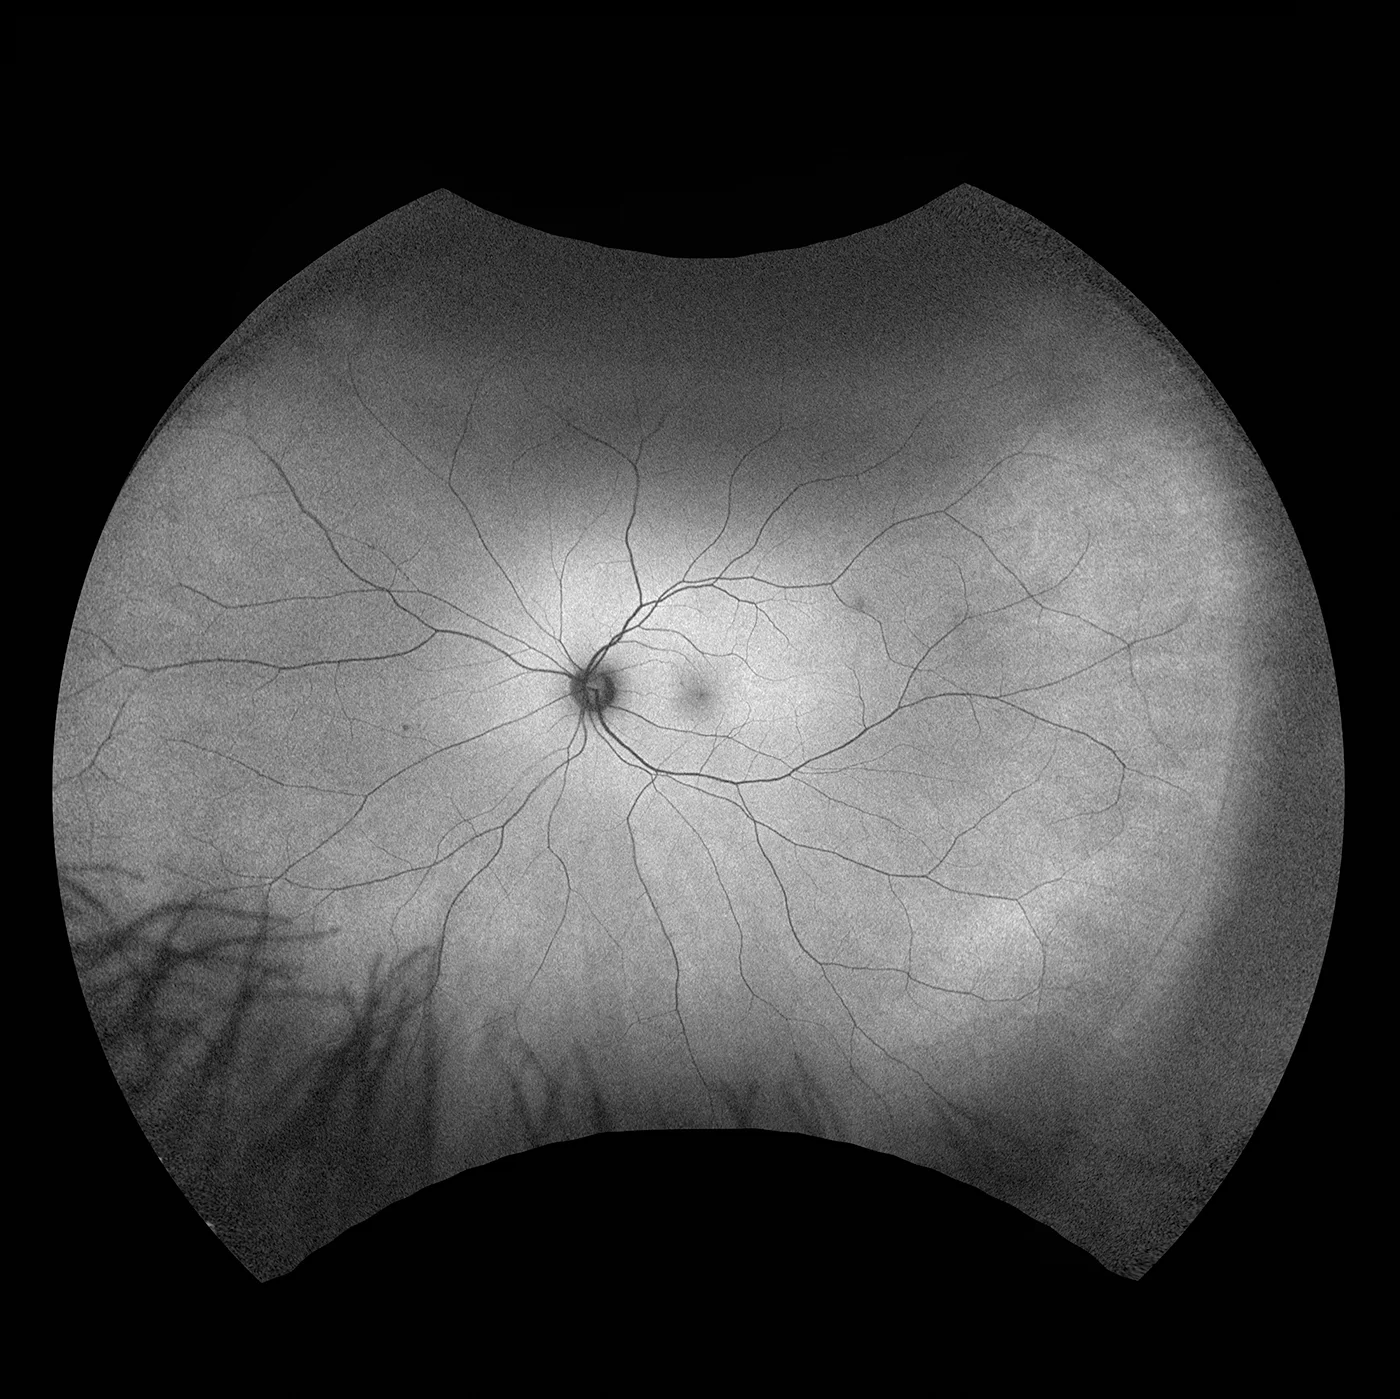

Optos führte die UWF™ (Ultra-Weitwinkel Bildgebungstechnologie) ein mit der Augenärzte Augenpathologien entdecken, diagnostizieren, dokumentieren und behandeln können, die sich zuerst in der Peripherie zeigen und mit konventionellen Untersuchungsmethoden und Geräten zunächst unentdeckt bleiben können. Jedes unserer Geräte für hochauflösende Ultra-Weitwinkel-Bildgebung erfasst mittels Laser Scanning Technologie in einer einzigen Aufnahme mehr als 80 % bzw. 200° der Netzhaut. Eine vollständige Liste unserer Geräte mit Ultra-Weitwinkel Bildgebungstechnologie finden Sie unten.

Silverstone RGB setzt neue Maßstäbe in der Netzhautbildgebung. Es ist das einzige Gerät, das in einer einzigen Aufnahme farbgetreue 200°-optomap-Ultraweitwinkelbilder erfasst - mit einem nahtlos integrierten, geführtem Swept-Source-OCT. Zum ersten Mal können Augenärzte in einem Gerät auf neun aussagekräftige Bildgebungsmodalitäten zugreifen, die jeweils für die Darstellung von Pathologien in der gesamten Netzhaut ausgelegt sind.

optomap verbessert nachweislich die Erkennung von Pathologien, das Management von Erkrankungen und Arbeitsabläufe in Praxen und Kliniken. Mit nun neun Modalitäten zur Netzhautbildgebung, darunter integriertes peripheres Swept-Source-OCT, erleichtert Silverstone RGB die Untersuchung der Netzhaut vom Glaskörper bis zur choroidal-skleralen Grenzfläche.

- Fluoreszenzangiographie